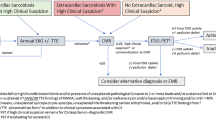

Both the Heart Rhythm Society (HRS) expert consensus statement and a recent positional statement from the Cardiovascular and Inflammation and Infection Committees of the European Association of Nuclear Medicine, the European Association of Cardiovascular Imaging, and the American Society of Nuclear Cardiology recommend either cardiac magnetic resonance (CMR) or 18-fluorodeoxyglucose positron emission tomography (18F-FDG PET), for patients with any significant abnormality on echocardiography and suspected CS, with CMR being a preferred initial imaging choice [38, 39••]. Diagnosis of CS with CMR has a 100% sensitivity and specificity of 78%, greatly surpassing echocardiography [39••, 40].

Despite several disadvantages and radiation risks associated with 18F-FDG PET, several studies have shown increased sensitivity and specificity when compared to other imaging modalities, including Gallium-67 uptake studies, Thallium-201 perfusion studies, and 99mTc imaging [60,61,62]. Some of its main advantages when compared with CMR are the ability to perform the tests in patients with implantable cardioverter-defibrillators and the ability to distinguish active inflammation from scar [63]. A recent small study out of France on patients with biopsy-proven sarcoidosis and suspected cardiac involvement reported 100% sensitivity and 91% specificity of FDG-PET/CT findings according to JMHW criteria [64].

There are limited studies comparing CMR to 18F-FDG PET, but one small study suggested that 18F-FDG PET has higher sensitivity (88%) when compared to CMR (75%). This study was quite small however, with only eight patients, and the results were not statistically significant [58, 65•]. A list of studies utilizing CMR and PET in patients with systemic sarcoidosis, known or suspected CS, and their respective sensitivities/specificities for cardiac involvement identification can be seen in Table 1. Initial reports also assume benefit of PET to reliably monitor disease progression and therapeutic monitoring of anti-inflammatory or immunosuppressive therapy [90] for CS, response to ablation therapy in ventricular arrhythmia patients using lesion metabolic activity (LMA) which correlated with a 20-fold higher risk of MACE in non-responders (p = 0.007) and may even parallel systolic function (p = 0.003) [91•], and association with higher adverse event rates in those with high-degree AVB [92]. Novel ECG parameters of ventricular remodeling (septal and inferolateral) and diffuse QRS fragmentation have also been found to have a strong association with myocardial FDG uptake on PET scans in sarcoidosis patients in a recent Finnish study of 133 patients [93]. FDG PET has also been shown to diagnose CS in asymptomatic patients [94] as this modality allows for detection of inflammation and infiltration via metabolic activity at the cellular level [95•]. In addition, in cases where myocardial LGE usually persists and T2-weighted edema CMR imaging may be unreliable, PET can reveal reduced FDG uptake that can signify a successful response to therapy in myocardial CS [96, 97].

Imaging classification for CS includes normal results (normal perfusion and 18F-FDG uptake), progressive disease (a moderate perfusion defect and increased 18F-FDG uptake), and fibrous disease (severe perfusion defect and minimal or no 18F-FDG uptake) [66]. Additionally, other quantitative techniques with 18F-FDG PET have been developed, like FDG-volume intensity detection, coined cardiac metabolic activity (CMA), which has been independently associated with adverse cardiac events in patients with CS [98•]. In summary, both imaging modalities, 18F-FDG PET and CMR, are very useful in CS and can be used in conjunction to diagnose and evaluate CS. Fibrosis can be identified as LGE on CMR, and inflammatory infiltration can be detected via increased 18F-FDG uptake on PET. Each modality can highlight different pathophysiologic processes in CS, and for this reason, both studies are valuable tools to diagnose and monitor the progression of the disease process.

F. Simultaneous hybrid cardiac imaging: 18F-FDG PET/CMR

Recently, some centers have taken on a hybrid imaging approach by combining 18F-FDG PET with CMR [115]. A small single-center study (N = 51) compared simultaneous 18F-FDG PET and LGE on CMR to current accepted diagnostic imaging modalities (18F-FDG PET alone and CMR alone). This study found that simultaneous hybrid imaging was superior to conventional imaging in terms of sensitivity (94%), specificity (44%), positive predictive value (76%), and negative predictive value (80%). The sensitivity for 18F-FDG PET is 85% and LGE on CMR is 82%. The prevalence of CS in this patient population was 65% (N = 33) [88]. Simultaneous hybrid cardiac imaging allows for high-resolution morphologic and functional data collection via LGE-CMR [95•] while retaining the ability to assess for myocardial viability, perfusion, inflammatory metabolism processes, and abnormal cardiac deposition via 18F-FDG PET. Compared to PET-CT, 18F-FDG PET CMR offers many advantages, including attenuation correction without additional radiation, detection of edematous tissue, and improved image quality in regard to myocardial viability, perfusion, cardiac morphology, and function [95•]. Recent studies also predict that hybrid cardiac imaging may allow clinicians to differentiate between active and inactive disease, as both positive PET and LGE on MRI suggest active CS, while PET-negative and LGE MRI-positive imaging may correlate with inactive disease with residual fibrosis [95•]. This mentioned benefit may aid in the monitoring of CS and response to therapy [116]. As both 18F-FDG PET and CMR are indicated imaging studies for the evaluation of CS [83], and there is no clear consensus on which modality is superior [104, 117], simultaneous hybrid cardiac imaging should be considered.

Framework of combined PET/CMR studies establishes a new monumental mark in our role as imagers and caregivers for these patients. The combination of CMR and FDG-PET imaging may add significant incremental benefit for many patients. Vita et al. demonstrated this in a recent paper with utilization of CMR, FDG-PET, and combination of both in assessment of the likelihood of CS and guidance of patient management. The combination of FDG-PET and CMR image data reclassified 45% (high probable and higher likelihood groups) of patients compared with single-modality imaging [118•, 119]. On the contrary, Dweck et al. postulated in a recent prospective combined PET/MRI study only 32% of their patients with both PET and MRI (LGE)-positive tests to suffer from active CS. As mentioned previously, it is important to keep in mind that PET-negative findings with positive LGE in MRI can be rather considered as inactive CS with remaining scar [87, 95•].